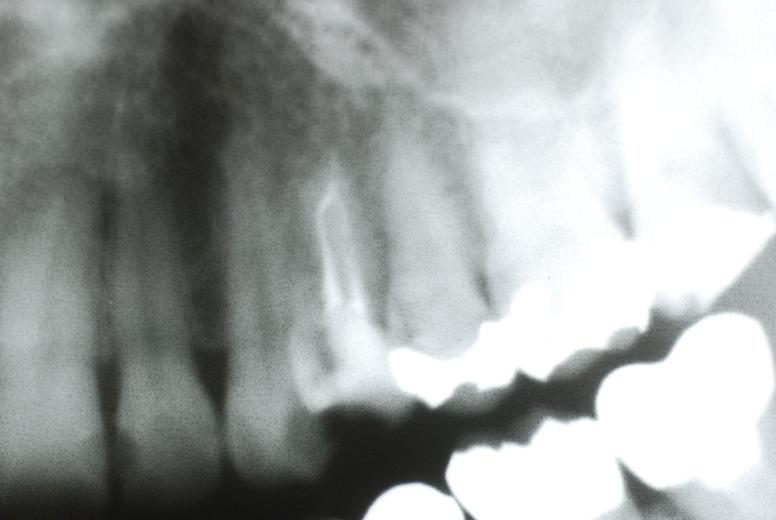

入れ歯の話から入りました。色々不満で注文があるようです。でも話が一段落して口腔内を調べると殆どの歯が重症で抜けそうな歯だらけなのです。

なぜ病気になるのかわからない方が多すぎます。歯が抜けるのは病気だからです。病気を治さずに何かお口の中に入れても土台である歯が抜けてしまっては同じことなのです。

何故歯が悪くなるのか、歯周病で抜けるのか分からなければ何を入れても歯は悪くなり抜けていくのです。